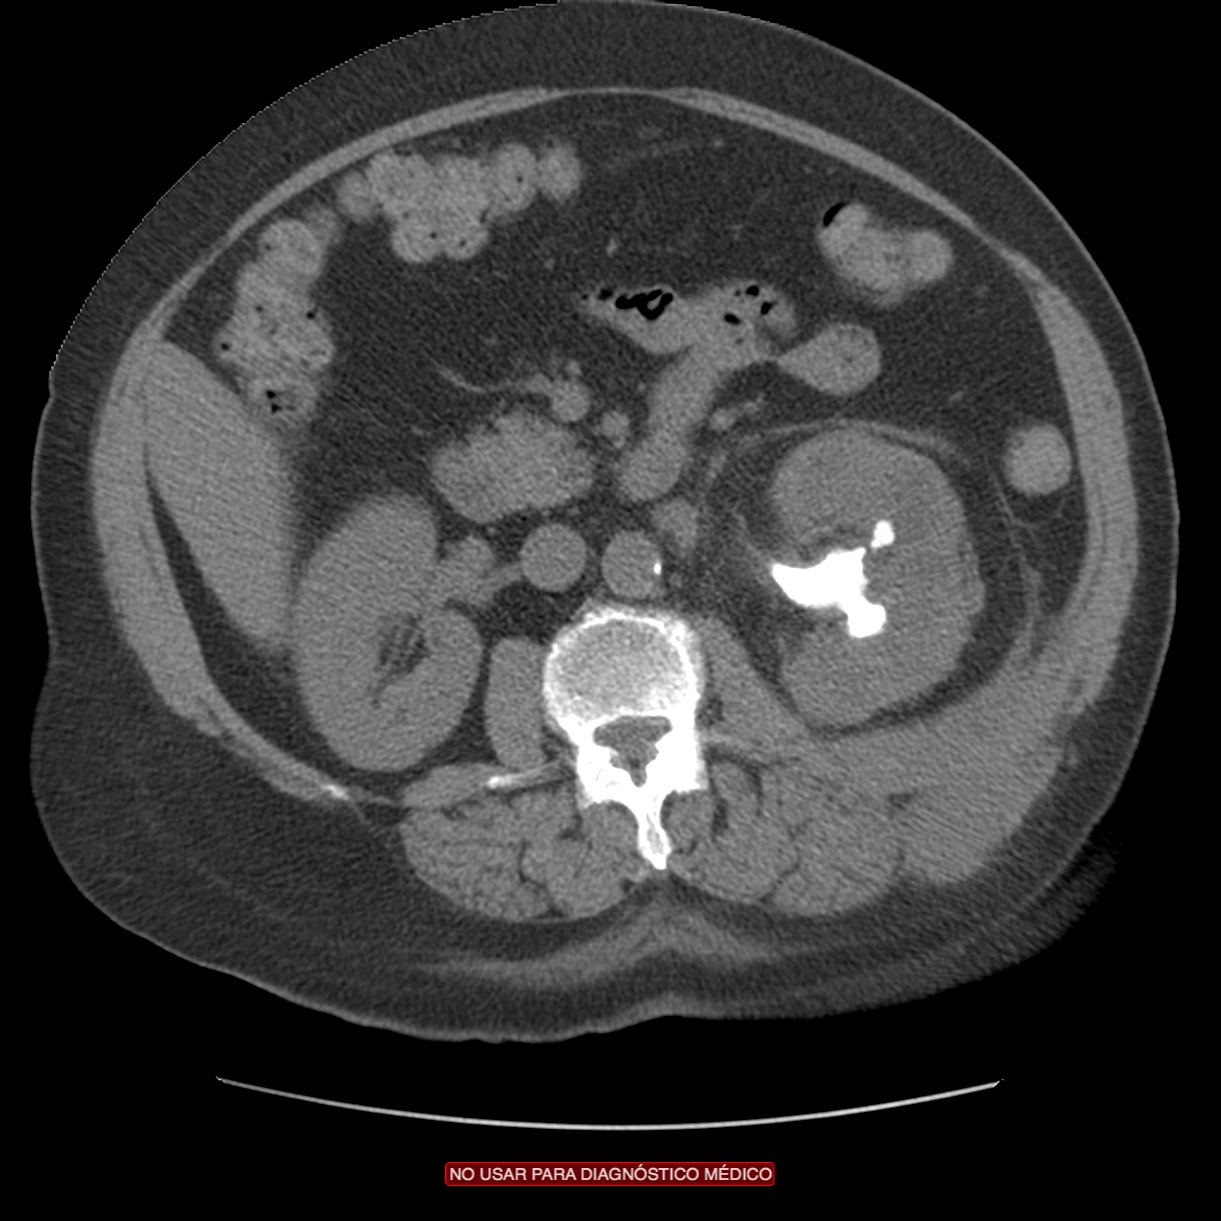

CASO 2: Paciente de 68 años con dolor en flanco izquierdo, fiebre y malestar general. A la exploración existe enrojecimiento de la piel con sensación de masa palpable y puño percusión muy positiva.

El paciente es alégrico al Iodo. Se realiza TC sin contraste para ampliar estudio.

Todos estos hallazgos están en relación con una Pielonefritis Xantunogranulomatosa que afecta al riñón derecho junto con una colección que ha fistulizado a región lumbar.